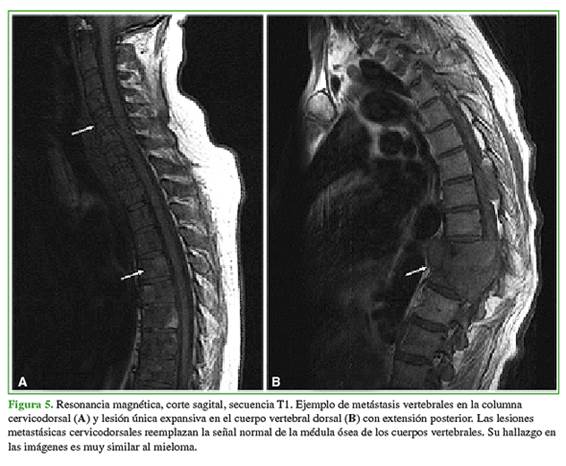

La resonancia magnética es un estudio más sensible para detectar lesiones múltiples en comparación con la radiografía estándar y la tomografía computarizada. Se han descrito cinco patrones: señal normal de la médula ósea, compromiso difuso, lesión focal, lesión combinada difuso-focal y parcheado. Las secuencias de resonancia magnética más utilizadas para la evaluación de la médula ósea son las convencionales T1 y T2. En la secuencia T1, la señal es típicamente baja y es alta en la secuencia T2 con supresión grasa. Las lesiones muestran refuerzo de la señal en secuencia T1 con medio de contraste. Suelen presentar una difusión (DWI) restringida, en comparación con la señal baja de la médula normal.

El principal diagnóstico diferencial son las metástasis óseas generalizadas (Figura 5). Un hallazgo en las imágenes que favorece el diagnóstico de metástasis óseas frente al de MM es el compromiso de pedículos vertebrales en la extensión vertebral del tumor frente al compromiso aislado o predominante del cuerpo vertebral.